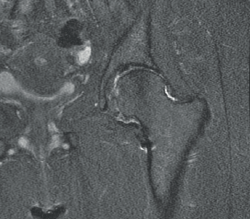

Se presenta el caso de una paciente de 49 años, que consulta por dolor y cojera de unos 2 años de evolución, a expensas de la cadera izquierda. Como antecedentes destaca una cirugía en la adolescencia en dicha cadera, sin conocer la causa ni aportar documentación. La exploración física mostraba dolor en flexión y rotación interna de la cadera, con una maniobra de choque anterior positiva. El examen radiológico simple (Figura 1) evidenciaba una gran exostosis ósea aislada en la transición cabeza-cuello femoral, sin objetivarse otras lesiones exofíticas asociadas. La resonancia magnética mostraba una exostosis ósea en la cara anterolateral del cuello femoral de 21 × 14 mm de diámetro (Figura 2) y signos compatibles de rotura del labrum anterosuperior.

Figura 2. A y B: corte axial de resonancia magnética (RM) en secuencia T1 (A) y corte coronal de RM en secuencia T2 (B) que evidencian una exostosis ósea de gran tamaño en la superficie anterolateral del cuello femoral; C: corte coronal en secuencia T2 que evidencia exostosis en el cuello femoral y signos compatibles con rotura del labrum anterosuperior.